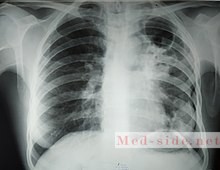

Диагноз туберкулеза считается установленным, если у пациента имеются клинико-рентгенологические признаки заболевания, но отсутствует бактериовыделение и гистологическое подтверждение диагноза.